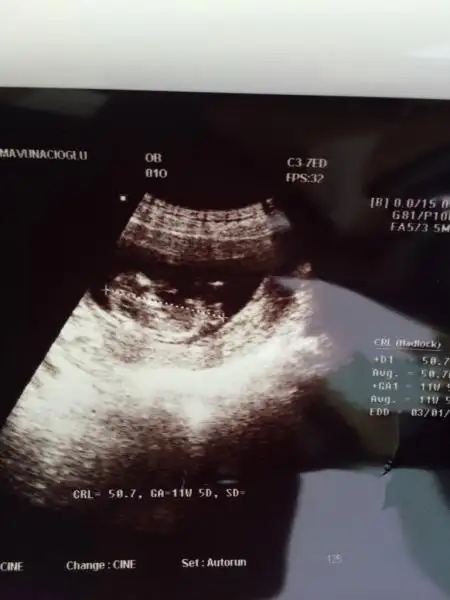

Fananaycım bunada yorum yapabılırmısın bu arkadasımın bebegının fotosu